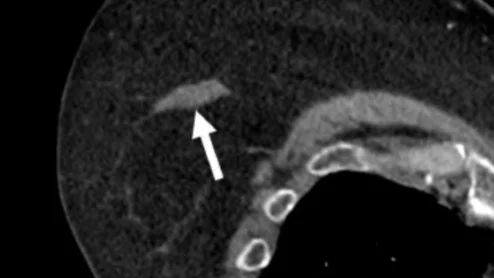

AI algorithm spots AAA on abdominal CT scan

The opportunistic screening helps identify patients in need of monitoring and/or intervention without disrupting workflows.